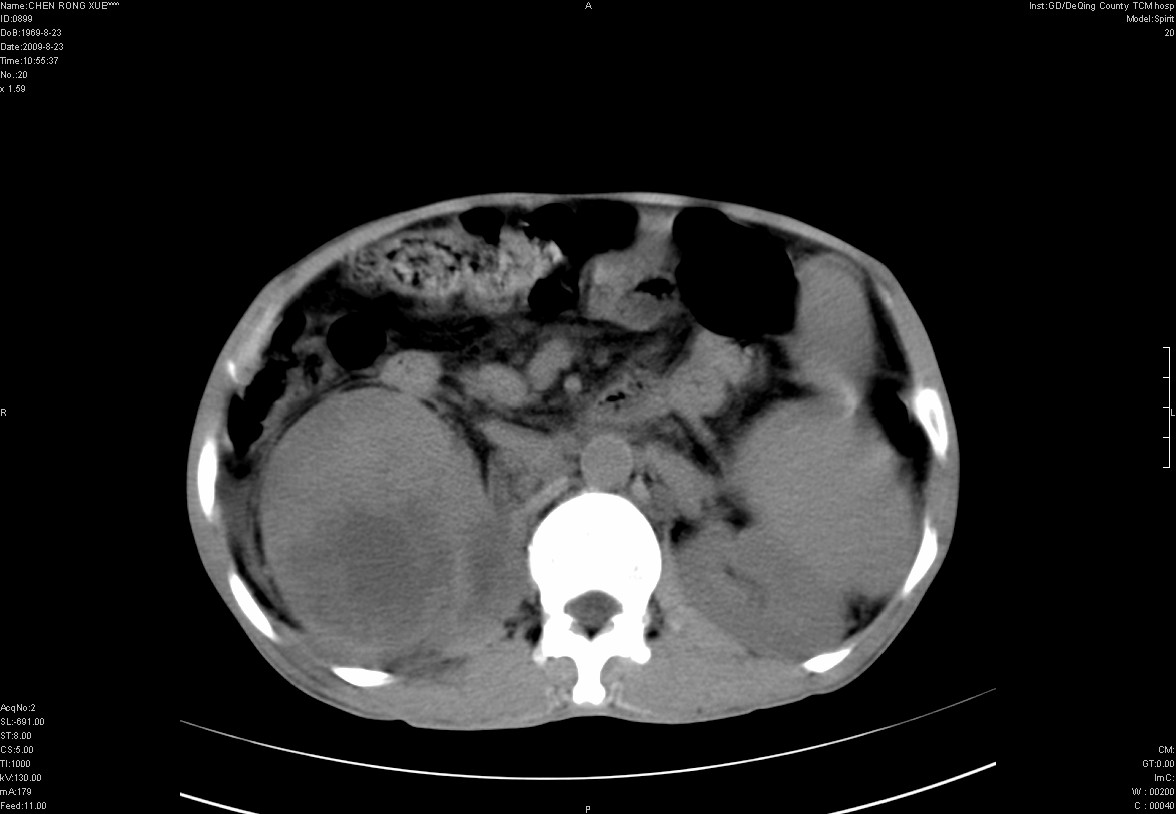

以下是引用zxl51642在2009-8-23 12:56:00的发言:[br]1、肝硬化、脾大;2、慢性胆囊炎;3、右肾占位并右侧腰大肌受侵,考虑恶性可能性大,建议增强扫描进一步检查。

以下是引用qiuleiyu在2009-8-23 15:17:00的发言:[br]1、慢性肝病,肝硬化,脾大,门脉高压。胆囊小结石。[br]2、右肾明显肿大,伴片状低密度灶,累及右侧腰大肌,肿瘤及炎症性病变皆有可能大,建议增强。

以下是引用zjzjr在2009-8-23 17:42:00的发言:[br]1、慢性肝病,肝硬化,脾大,门脉高压。胆囊小结石。[br]右肾脓肿波及肾周,建议增强

以下是引用dyqct在2009-8-23 16:53:00的发言:[br][quote]以下是引用qiuleiyu在2009-8-23 15:17:00的发言:[br]1、慢性肝病,肝硬化,脾大,门脉高压。胆囊小结石。[br]2、右肾明显肿大,伴片状低密度灶,累及右侧腰大肌,炎症性病变可能,建议增强。